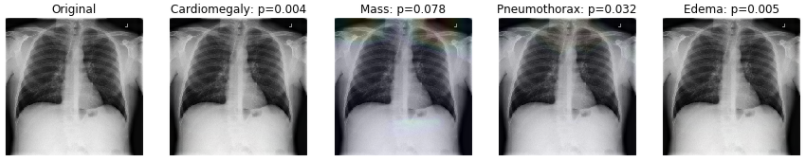

5.2 Visualizing Learning with GradCAM

: GradCAM 기술을 사용하여 병리학적 상태를 예측하기 위해, 이미지의 중요한 영역을 강조하는 히트맵을 생성

: 먼저 작은 Training 셋을 로드하고, 앞서 AUC 측정값이 가장 높은 4개의 클래스를 살펴볼 것

: 몇 가지 특정 이미지들을 확인

util.compute_gradcam(model, '00008270_015.png', IMAGE_DIR, df, labels, labels_to_show)

# Expected output

Loading original image

Generating gradcam for class Cardiomegaly

Generating gradcam for class Mass

Generating gradcam for class Pneumothorax

Generating gradcam for class Edema

: P 값은 정답 클래스의 softmax probability를 의미함